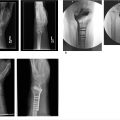

Corrective osteotomy techniques allow the hand surgeon to address symptomatic rotational, angular, and length deformities that occur following malunion of metacarpal fractures. A number of techniques including closing wedge osteotomy, opening wedge osteotomy, and derotation osteotomy are available to address the specific three-dimensional pathoanatomy of the malunion.

2.0/2.4 mm metal plates and screws are typically used to achieve stable fixation of metacarpal osteotomy sites

Many plating systems include purpose-made corrective osteotomy plates with oblong holes that facilitate angular stability, while permitting rotational adjustment, which allows the surgeon to “dial in” the degree of correction desired

The use of locking screws minimizes undesired deformation of osteosynthesis site during fixation